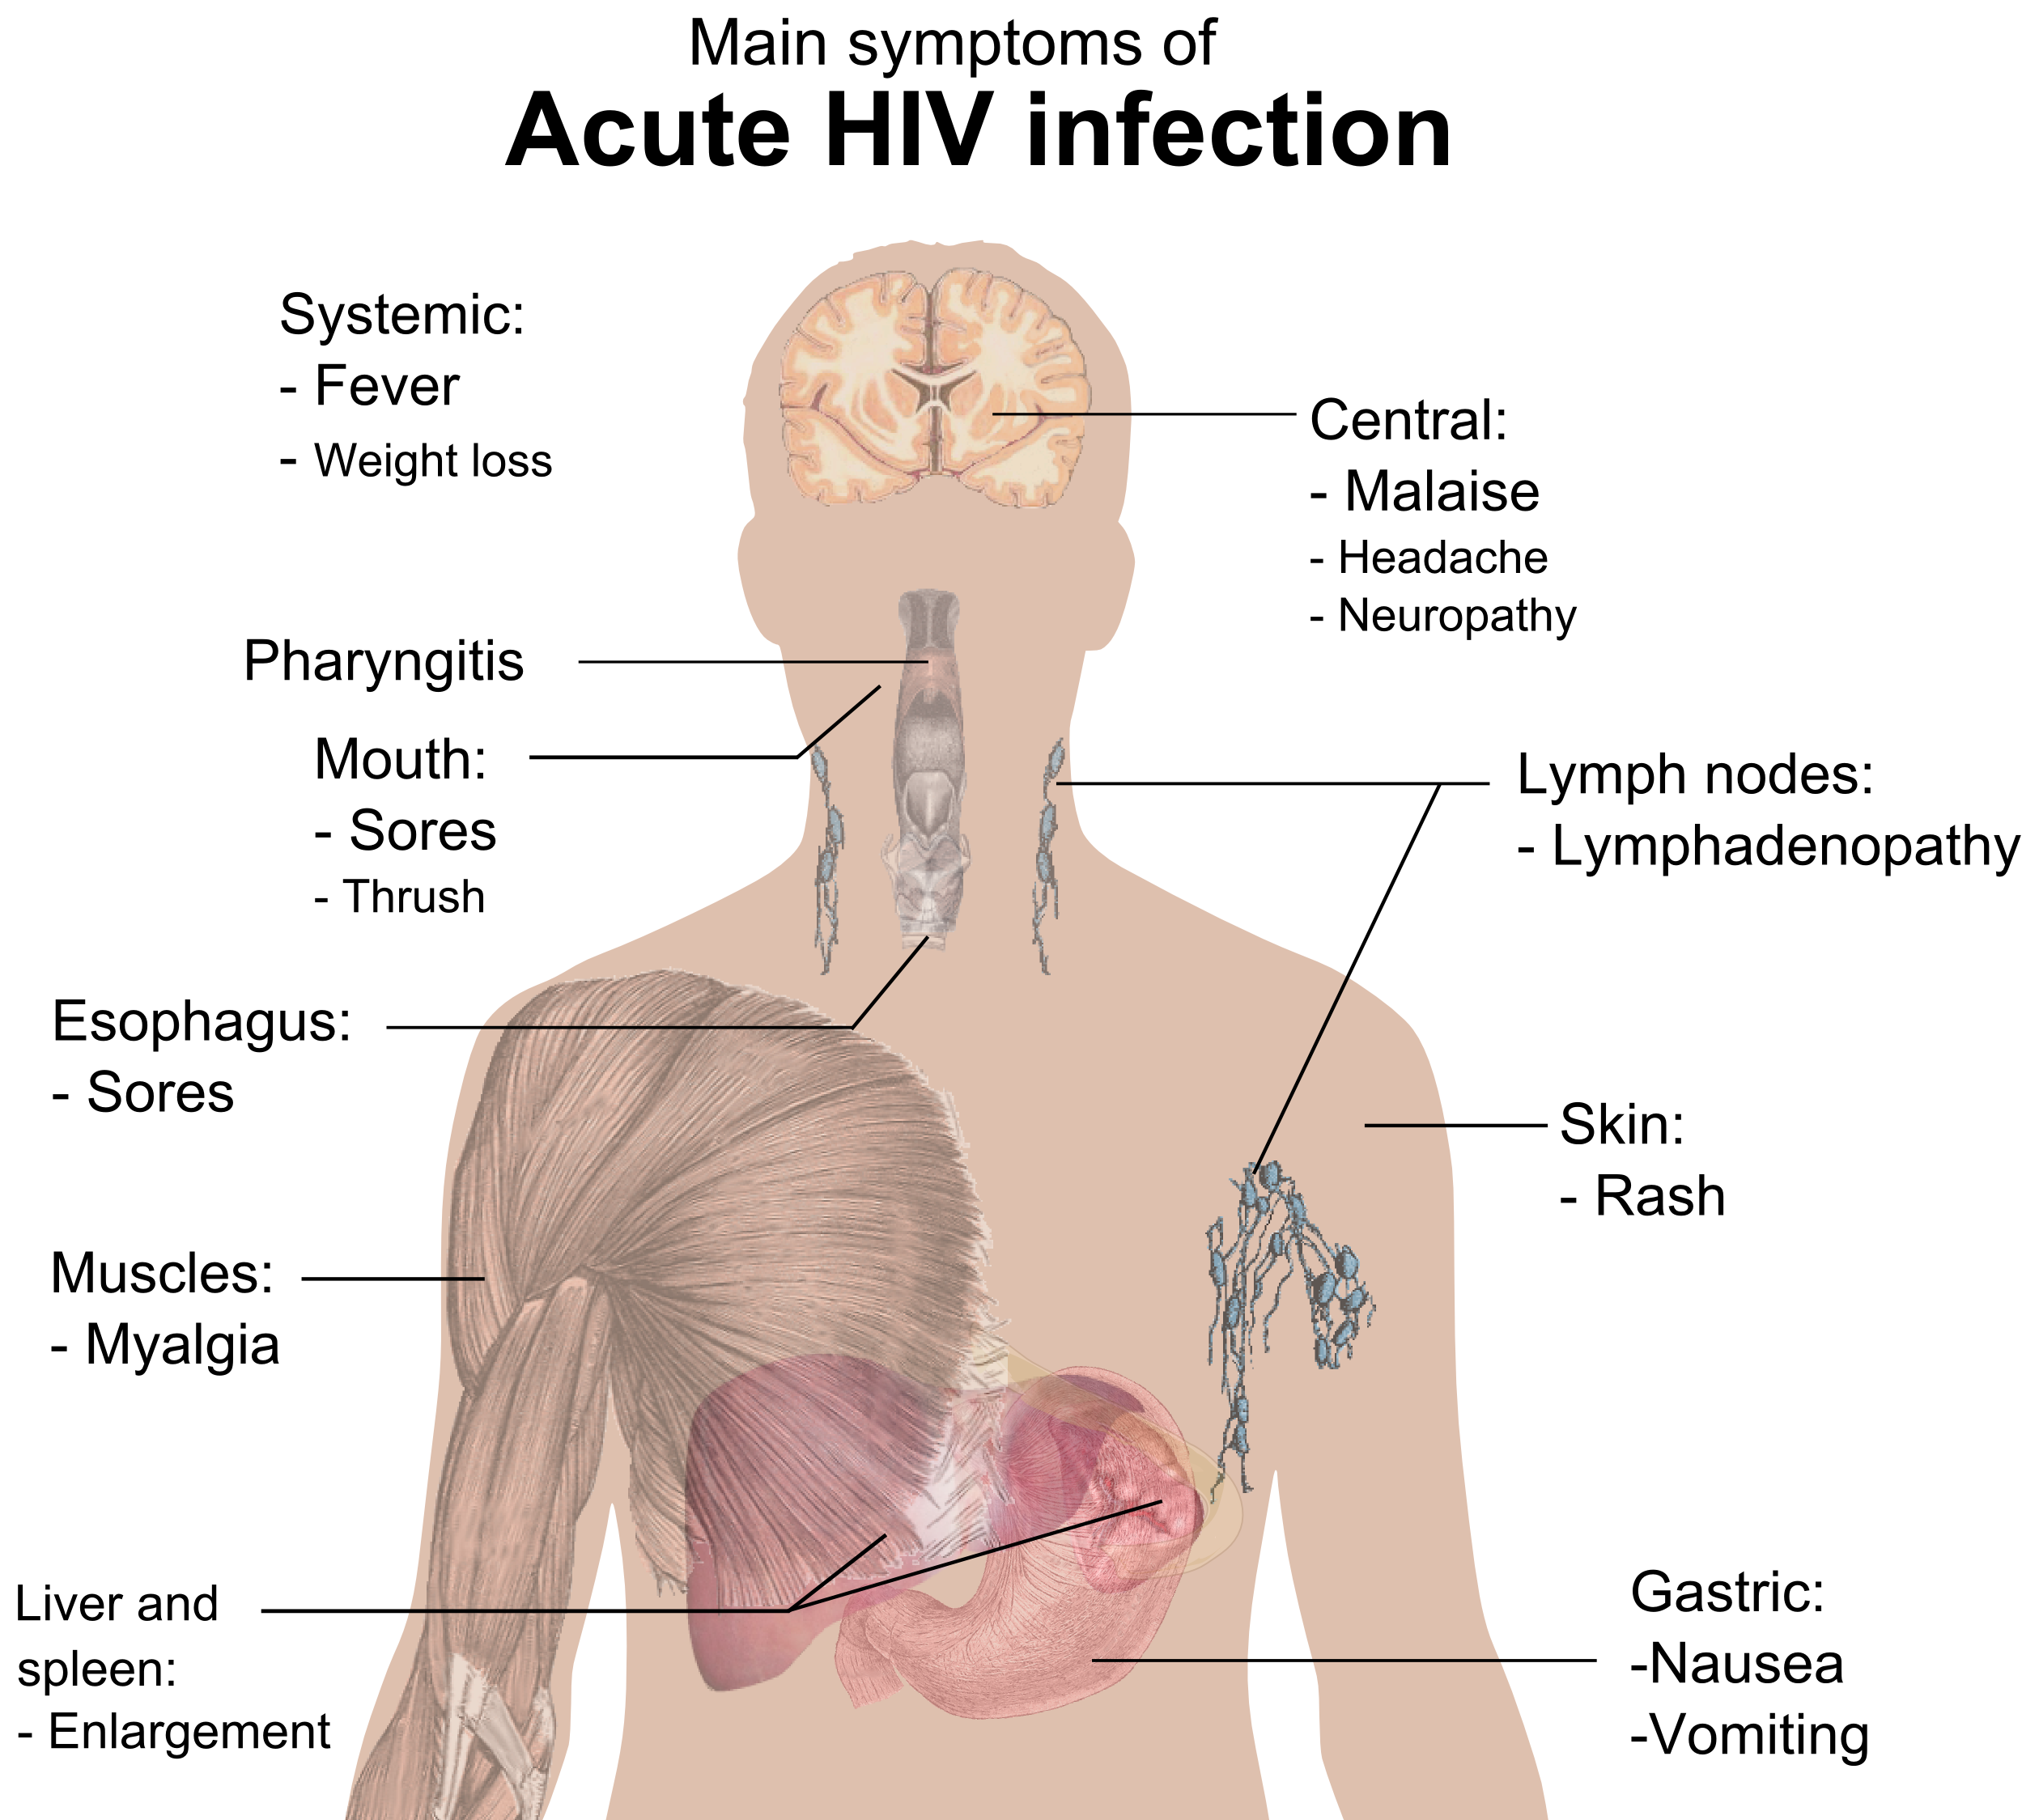

급성 HIV 감염은 HIV 감염의 첫 번째 단계이다.[1] 이 시기(보통 노출 후 며칠에서 몇 주) 동안 감염된 사람의 50~90%가 인플루엔자 또는 단핵구증과 유사한 질병을 앓는다.[2][3]

가장 흔한 증상은 다음과 같다.[4]

덜 흔하게 나타나는 증상은 다음과 같다.[4]

감염된 사람은 이러한 증상을 모두, 일부 또는 전혀 경험하지 않을 수 있다.[4] 증상은 평균 28일 동안 지속되며, 보통 최소 일주일 이상 지속된다.[5]

이러한 증상의 비특이적인 특성 때문에 HIV 감염의 징후로 인식되지 않는 경우가 많다. 환자가 의사나 병원에 가더라도 동일한 증상을 보이는 더 흔한 전염병 중 하나로 오진되는 경우가 많다. 따라서 이러한 주요 증상은 HIV 감염을 진단하는 데 사용되지 않는다. 그러나 이 기간 동안 환자가 훨씬 더 전염성이 높기 때문에 증후군을 인식하는 것이 중요할 수 있다.[6]